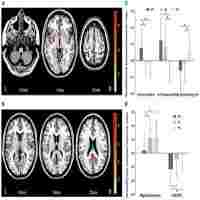

| Description | Journal: Human brain mapping Resting‐state fMRI (RS‐fMRI) has become a useful tool to investigate the connectivity structure of mental health disorders. In the case of major depressive disorder (MDD), recent studies regarding the RS‐fMRI have found abnormal connectivity in several regions of the brain, particularly in the default mode network (DMN). Thus, the relevance of the DMN to self‐referential thoughts and ruminations has made the use of the resting‐state approach particularly important for MDD. The majority of such research has relied on the grand averaged functional connectivity measures based on the temporal correlations between the BOLD time series of various brain regions. We, in our study, investigated the variations in the functional connectivity over time at global and local level using RS‐fMRI BOLD time series of 27 MDD patients and 27 healthy control subjects. We found that global synchronization and temporal stability were significantly increased in the MDD patients. Furthermore, the participants with MDD showed significantly increased overall average (static) functional connectivity (sFC) but decreased variability of functional connectivity (vFC) within specific networks. Static FC increased to predominance among the regions pertaining to the default mode network (DMN), while the decreased variability of FC was observed in the connections between the DMN and the frontoparietal network. Hum Brain Mapp 37:2918–2930, 2016. © 2016 Wiley Periodicals, Inc. |